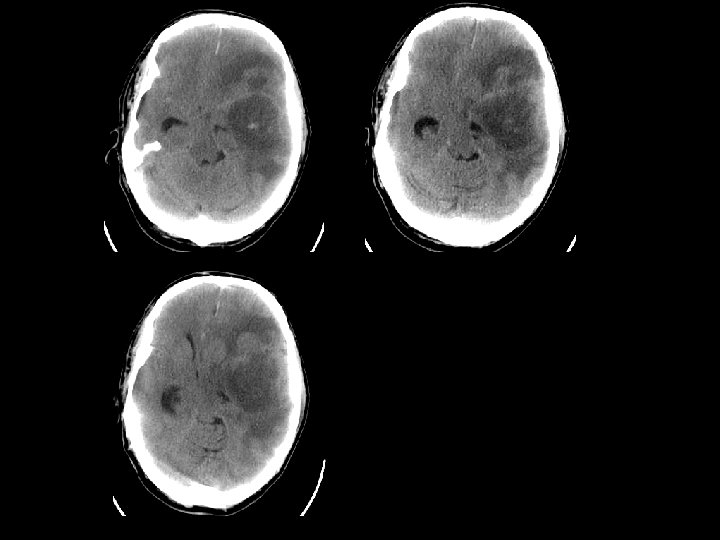

HERNIASI OTAK

HERNIASI SUBFALCIAL n Subfalcial: pergeseran girus cingulatum di bawah tepi bebas falx bersama dengan arteri pericallosal. n Dapat menimbulkan infark arteri serebri anterior

HERNIASI UNCAL n Pergeseran medial lobus temporal melalui n n n tentorial notch Pergeseran midbrain Effacement of the suprasellar cistern Pergeseran pedunculus cerebri kontralateral terhadap tentorium Pelebaran ipsilateral cerebello pontine angle Penekanan arteri serebri posterior

DOWNWARD HERNIATION n Caudal displacement of the thalamus and midbrain n Effacement of the perimensencephalic cistern and 4 th ventricle. n Dapat menyebabkan palsi N. III dan merusak pembuluh darah pons yang bisa menyebabkan perdarahan batang otak